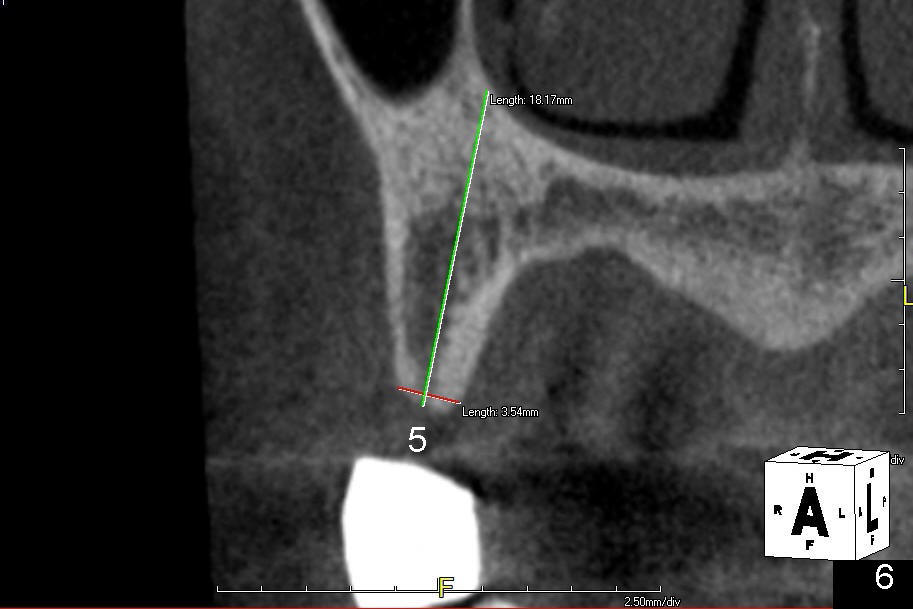

A 56-year-old lady lives out of state. She requests implant treatment for the upper right quadrants. Implants were removed by her previous care provider due to pain and infection. The premolars (Fig.1: #4,5) are provisionalized with a mini-implant (*). CBCT scans (Fig.1,2 (sagittal sections); Fig.3-6 (coronal section) show limited bone height involving the sites of the teeth #2 (Fig.1,3), 3 (Fig.2,4) and 4 (Fig.1,5). The buccolingual width is narrow at the sites of the teeth #4 and 5 (Fig.5,6).